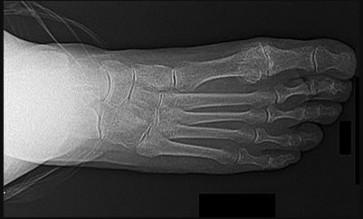

Question 19

A 45-year-old female presents with a painful bunion and clinically evident hypermobility of the first tarsometatarsal (TMT) joint. Weight-bearing radiographs demonstrate a hallux valgus angle of 40 degrees and an intermetatarsal angle (IMA) of 18 degrees.

Which surgical procedure is most appropriate to comprehensively address her pathology?

Explanation

The patient has a severe hallux valgus deformity (IMA > 15 degrees) combined with first TMT joint hypermobility. The Lapidus procedure (arthrodesis of the first tarsometatarsal joint) addresses both the severe metatarsus primus varus and the hypermobility of the first ray at its apex, making it the most appropriate and biomechanically sound choice for this specific clinical scenario.